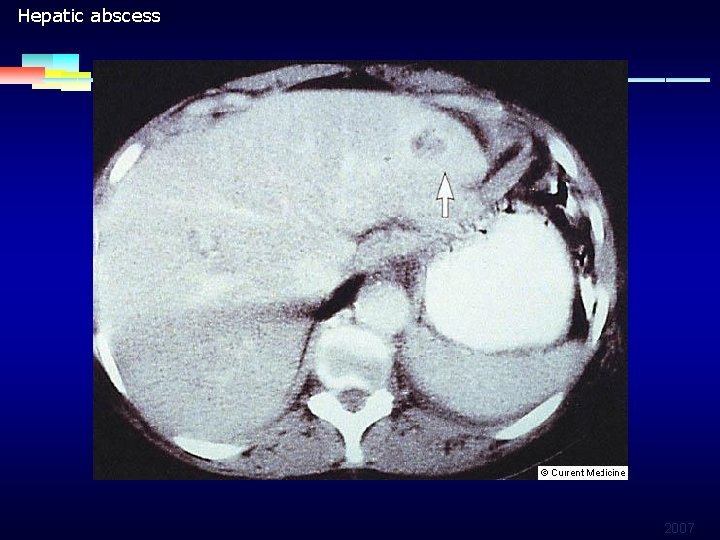

FUO INFECTION ASSOCIATED § Intra-abdominal or pelvic abscess Ø Ø Abscess 1/3 infection origin of FUO, most intra-abdominal or pelvic Vague localized abdominal pain Surgical complication or leakage of visceral contents Liver abscess: elevated ALK-p K. pneumoniae bacteremia in DM, alcoholism, Liver cirrhosis Liver echo may be negative, so abdominal CT is important for diagnosis 2007

Hepatic abscess 2007